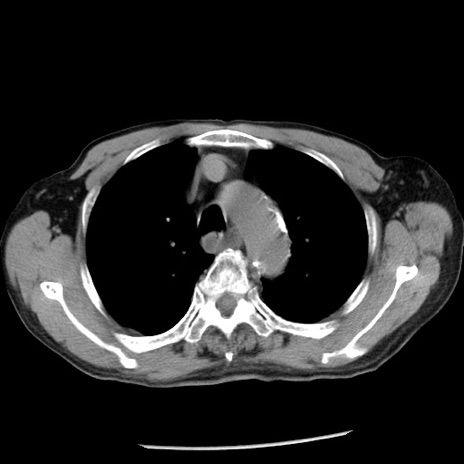

冠状断像

【症例】80歳代男性

【主訴】嘔吐

【現病歴】昨晩2回嘔吐あり、今朝になっても嘔吐あり。来院。

【既往歴】胃潰瘍

【身体所見】意識清明、BT 37.6℃、BP 166/95mmHg、HR 100bpm、SpO2 97%、腹部:平坦・軟、腸蠕動音聴取良好、圧痛なし。

【データ】WBC 21900、CRP 1.46